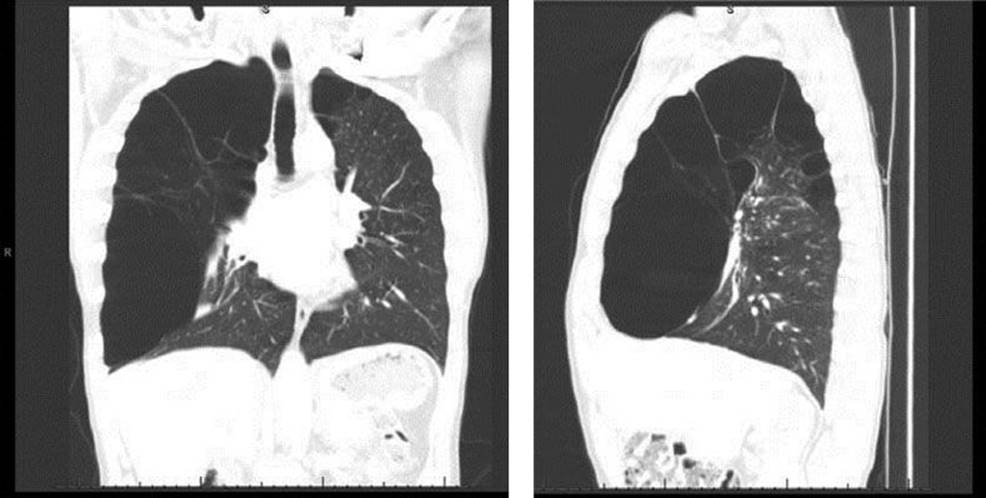

The most important aspect of the preoperative plan is selecting the appropriate patients based on severity of symptoms and CT imaging. Patients with dominant giant bulla with limited septations and compressed functional lung tissue are the ideal candidates for this procedure (Fig. 8.1).

Figure 8.1 Sagittal and coronal computed tomography images of the chest demonstrating a giant bulla compressing the right lower lobe and flattening the diaphragm.